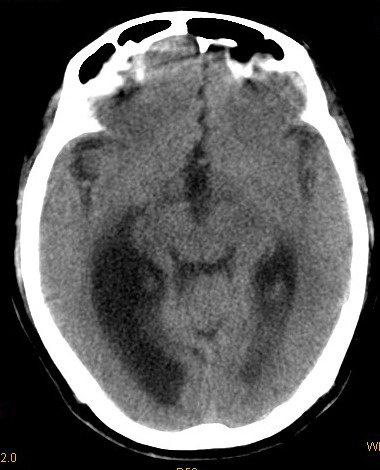

以下是引用卜一在2008-8-14 16:31:00的发言:[br]支持:巨脑回伴脑积水!另:胼胝体发育不良!

以下是引用同在2008-8-14 19:46:00的发言:[br]巨脑回伴积水,胼胝体发育不良.